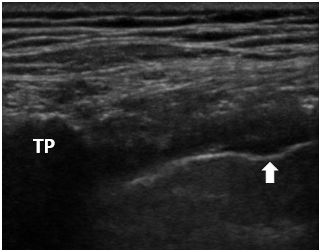

赤臨麻の図です。

傍脊椎腔に針をささなくても、

その延長上で注入すれば(図の矢印)

傍脊椎腔まで薬液が達します。